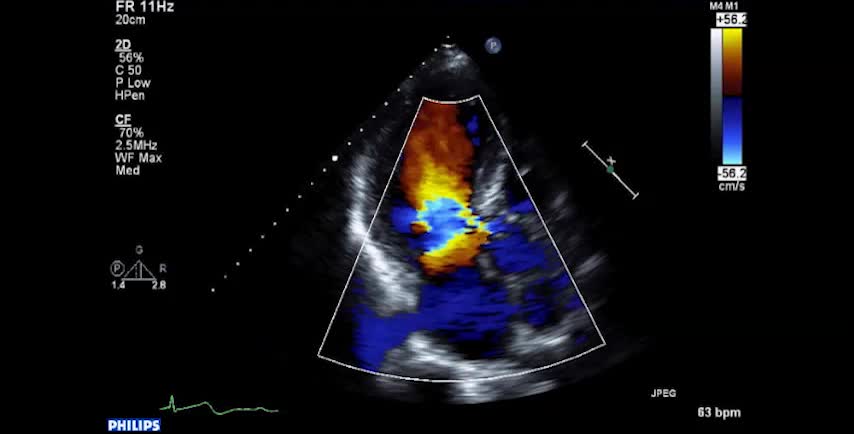

• 症例2 60代男性.僧帽弁逆流症

• 図5 僧帽弁後尖P2 逸脱によるMR a 胸骨右縁第2...

• 図5 僧帽弁後尖P2 逸脱によるMR a 心尖